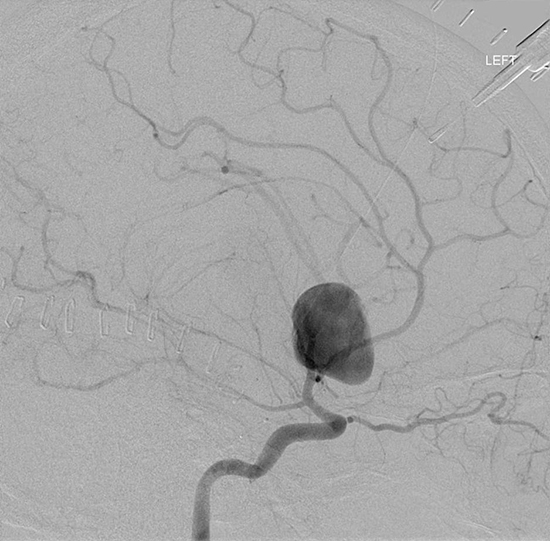

Figure 3: Aneurysmal Stroke (Subarachnoid Hemorrhage). The images below show a giant aneurysm that ruptured in a 30 year old patient, causing subarachnoid hemorrhage (SAH) and intraparenchymal hemorrhage (IPH or ICH). The image on the left is an axial CT scan showing the hemorrhaging and the aneurysmal sac in the brain near the top of the image. The image on the right is an angiogram showing a side view of the aneurysm and the cerebral vasculature. (Images courtesy of Dr. McMurtrey)